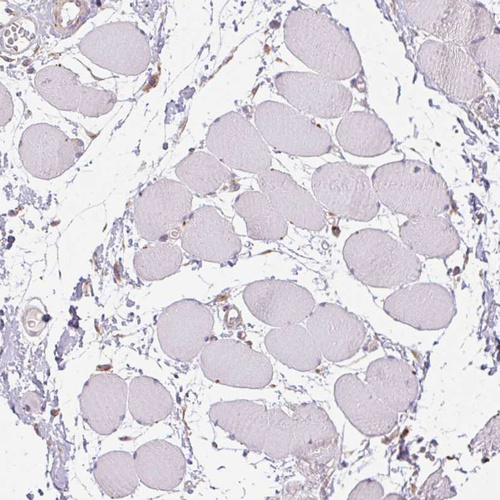

Immunohistochemistry analysis in human endometrium and skeletal muscle tissues using HPA061919 antibody. Corresponding ADH5 RNA-seq data are presented for the same tissues.